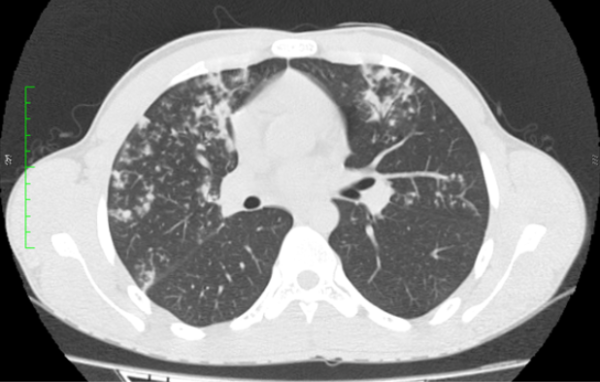

Paciente sexo masculino, 18 anos, sem comorbidades, com quadro arrastado de febre e perda ponderal há cerca de três meses. Foi realizado radiografia de tórax (não disponibilizada), com laudo inconclusivo. Optou-se por prosseguir investigação com tomografia computadorizada do tórax.

Diante das imagens, qual a melhor descrição e a principal hipótese diagnóstica?

CEscavação de paredes espessadas no lobo superior direito e nódulos com distribuição centrolobular dispersos pelo parênquima – tuberculose